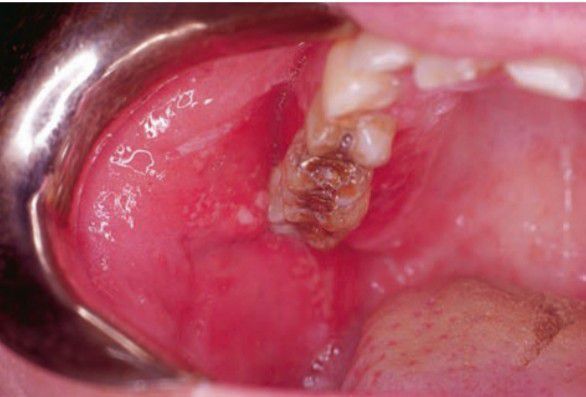

Contact allergy

Contact hypersensitivity of buccal mucosa and palatal gingiva. Lesions caused by direct contact with foreign antigen; erythema, vesicles, ulcers may be seen